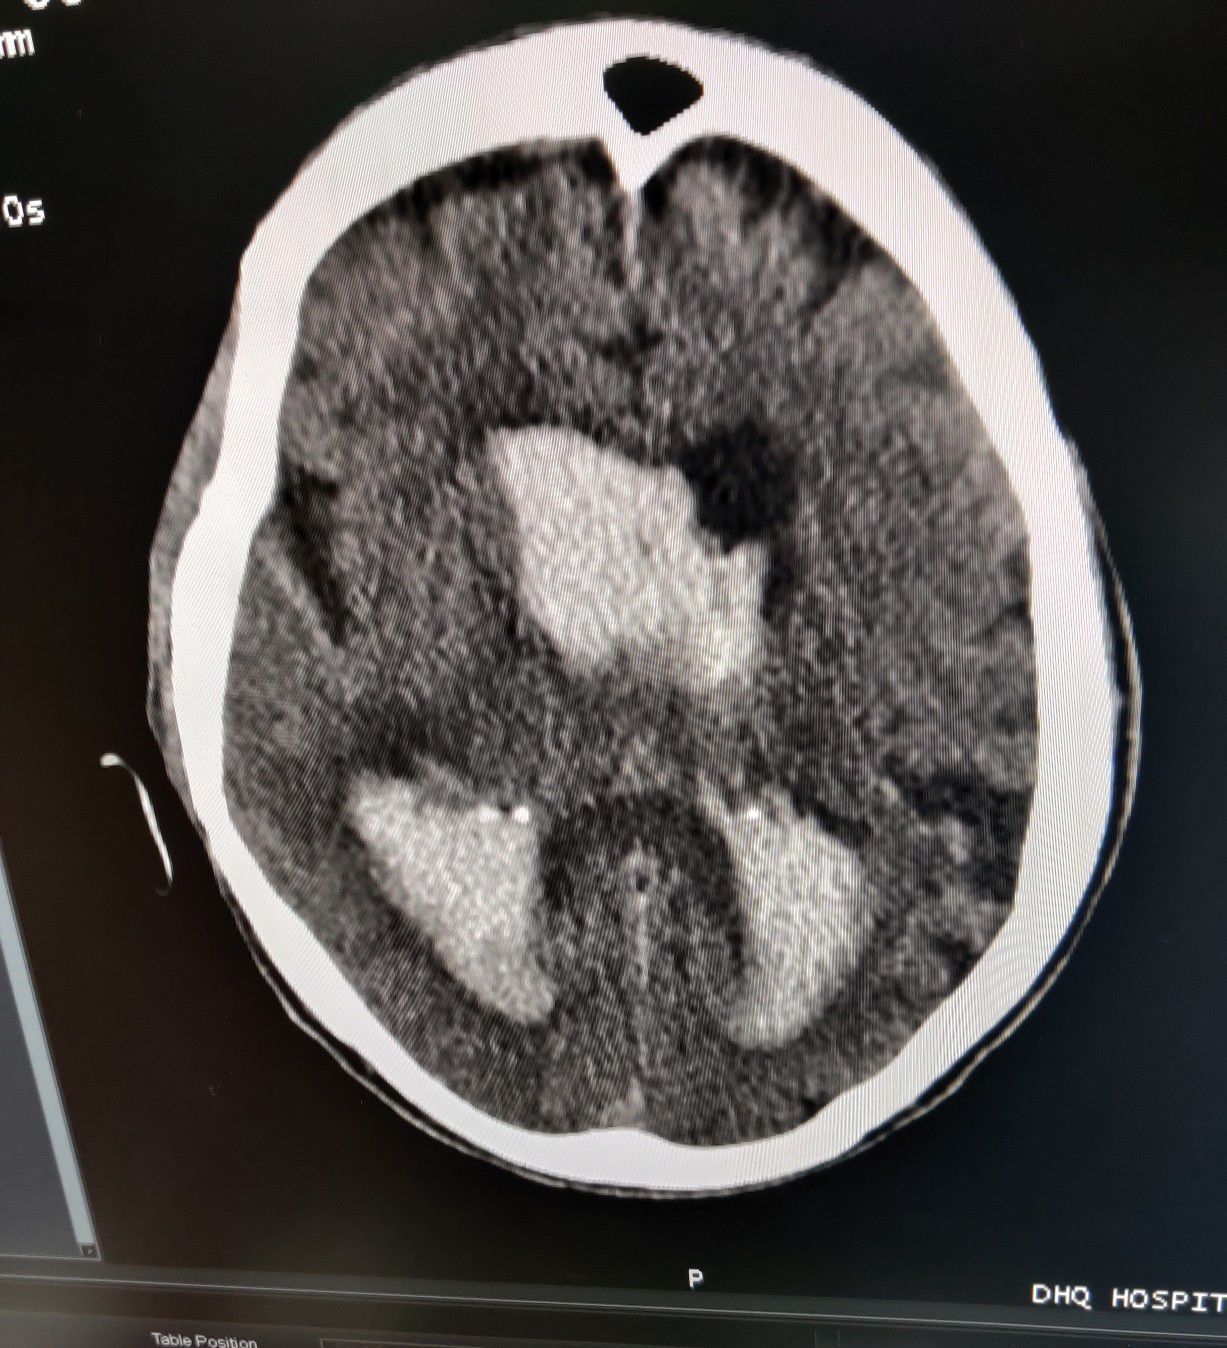

Hemorrhagic CVA

Emergency

Stroke

Hemorrhagic